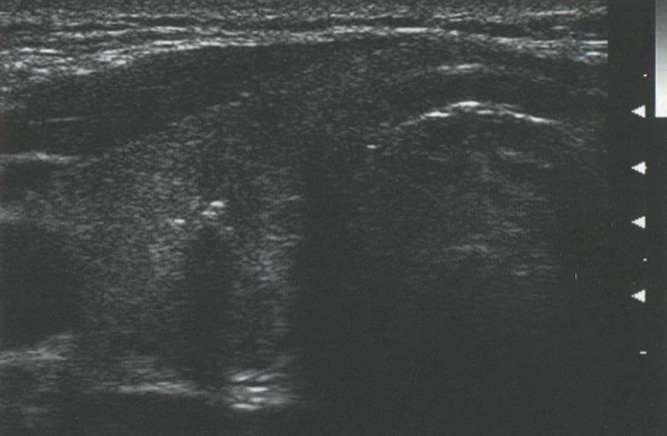

В то же время кистозные структуры проводят звук с очень маленьким затуханием, в результате этого интенсивность звуковых волн за ними намного выше, чем у прилежащих структур. Это приводит к акустическому усилению с ярким сигналом позади кистозных или анэхогенных структур. Это усиление может быть использовано для дифференциации кистозных и солидных узлов в ЩЖ. Рис. 2.12 показывает усиление сигнала.

Рис. 2.12. Усиление сигнала. Кистозные структуры проводят звук с незначительным затуханием, что проявляется в большей интенсивности звуковых волн позади таких образований. Усиление сигнала обычно возникает кзади от кистозного узла